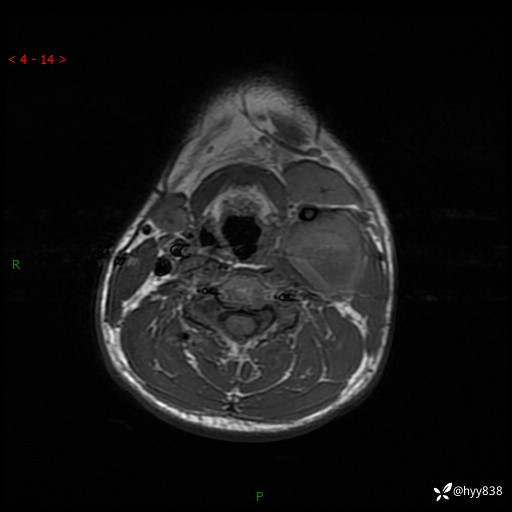

年轻小伙,发现左侧颈部肿物3年余,逐渐增大---结果公布~

现病史:患者约3年前因感冒发现左侧颈部长一肿物,约半个鸡蛋大小,无明显疼痛及其他不适,一直未行特殊处理。3个月前发现左侧颈部肿物变大,随后至当地市第二人民医院耳鼻喉科行左侧颈部彩超示:左侧颈部囊实混合性包块;喉部MPR示:左侧胸锁乳突肌内前方占位,累及左侧喉旁间隙,建议增强扫描。建议手术治疗。患者考虑。随后至我院肿瘤科就诊,行细胞学穿刺示:考虑血管源性肿瘤可能,建议进一步检查。建议至我院口腔科就诊,行颌面部MRI示:左侧颌下腺后方团状异常信号灶,建议增强。建议手术治疗。为求进一步治疗,门诊以“左侧颈部肿物”收入院。 起病以来,患者神志清、精神良好,饮食睡眠良好,大小便正常,体重未见明显变化。

颈部MRI平扫+增强